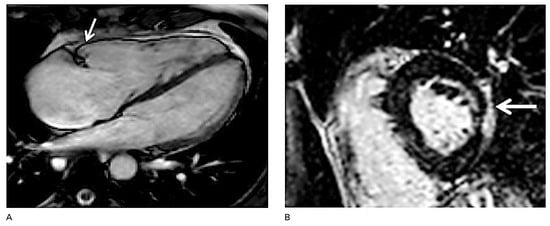

Figure 3.

Structural phenotypes of arrhythmogenic cardiomyopathy. A: Right ventricular (RV) dyskinesia in the RV subtricuspid area (arrow) during systole detected by cardiac magnetic resonance imaging (four-chamber view). The right ventricle is dilated (RV end-diastolic volume index 136 ml/m2, norm 65–102), and RV ejection fraction is reduced (RV-EF 38%, norm >45%). Regional RV dyskinesia in conjunction with RV dilation is considered a diagnostic criterion for classical ARVC diagnosis. Please also note that the right atrium is severely enlarged. B: Epicardial left ventricular late gadolinium enhancement detected by cardiac magnetic resonance imaging indicating biventricular involvement in another patient with biventricular ACM (arrow).